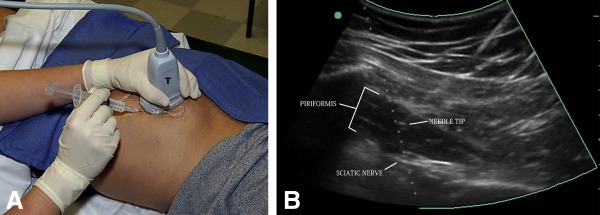

روش 2: در بخش با استفاده از سونوگرافی ابتدا محل ورود سوزن با مالیدن موادی تمیز و استریل می شود. سپس با تزریق داروی بی حسی در محل ورود سوزن آن محل بی حس می شود. سپس سوزن مخصوص با کمک دستگاه سونوگرافی به محل مورد نظر هدایت می گردد. پزشک سوزن را تا زمان رسیدن به عضله با استفاده از دستگاه سونوگرافی دنبال می کند.

سپس داروی کورتیکواستروئید و بی حس کننده موضعی به آرامی به محل مفصل تزریق می گردد. معمولا کل این فرایند بین 15 تا 20 دقیقه به طول خواهد انجامید.